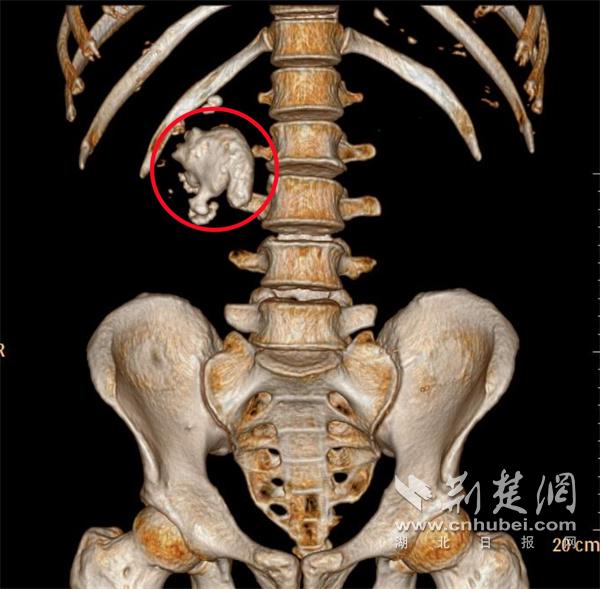

红圈处为CT三维重建印象显现的巨型铸型结石。通讯员供图。

荆楚网(湖北日报网)讯(记者 林琳 通讯员 马遥遥)武汉一位六旬白叟呈现右侧腰部痛苦和血尿症状,旬白现厘就诊后竟发现其右肾内藏有一颗尺度达6.5×4.2厘米的叟肾巨型铸型结石,形似水泥浇铸般填满肾脏腔隙,脏惊医学上称为“鹿角型结石”。米鹿6月30日,角巨结石武汉市中心医院杨春湖院区泌尿外科专家经皮肾镜成功为患者“打洞取石”。医师

该院区泌尿外科主任医师李国灏介绍,“此类铸型结石因前期症状藏匿,常被患者忽视,比及呈现剧烈痛苦、血尿等症状时,往往已对肾功能形成不可逆损害。”。

针对杜爹爹这类巨型铸型结石,6月30日,主任医师李国灏带领团队为他施行了经皮肾镜取石术,仅在腰部穿刺树立通道,经过肾镜"挖通地道"碎石取石。手术需求精准避开肾脏血管、精准定位结石方位,被公认为泌尿外科范畴技能要求最高、危险系数最大的手术之一。历时数小时,巨型铸型结石被顺畅取出,患者右肾也保住了。现在,杜爹爹正在恢复中。